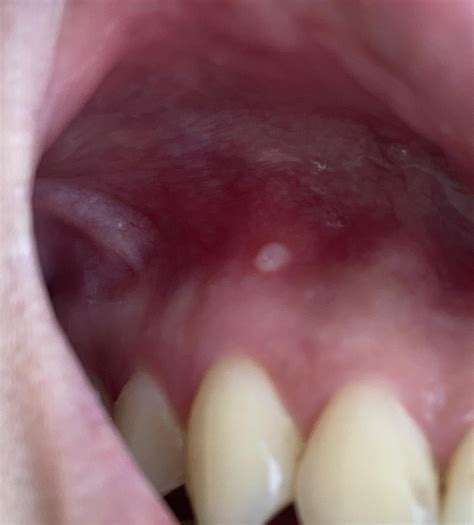

Discovering a pimple on gums can be an alarming experience, often leading to immediate worry about oral health. While it may look like a common skin blemish, a bump on your gum tissue—frequently referred to as a dental abscess or a fistula—is a signal that something deeper is occurring within your oral cavity. Unlike a pimple on your face, which is usually caused by clogged pores, a bump on the gum line is almost always related to bacterial infections, dental trauma, or underlying periodontal issues that require professional attention.

A pimple on gums is rarely just a localized skin issue. In the world of dentistry, this bump is often a drainage point for an infection located at the root of a tooth or deep within the gum pockets. When bacteria accumulate, the body attempts to fight off the infection, creating pus. Since the pus has nowhere else to go, it pushes through the soft gum tissue, resulting in a small, fluid-filled bump.

Identifying a pimple on gums involves more than just seeing the bump. Patients often report a range of sensations that help differentiate a dental abscess from a simple canker sore. If you notice any of the following, it is imperative to schedule an appointment with your dentist as soon as possible: